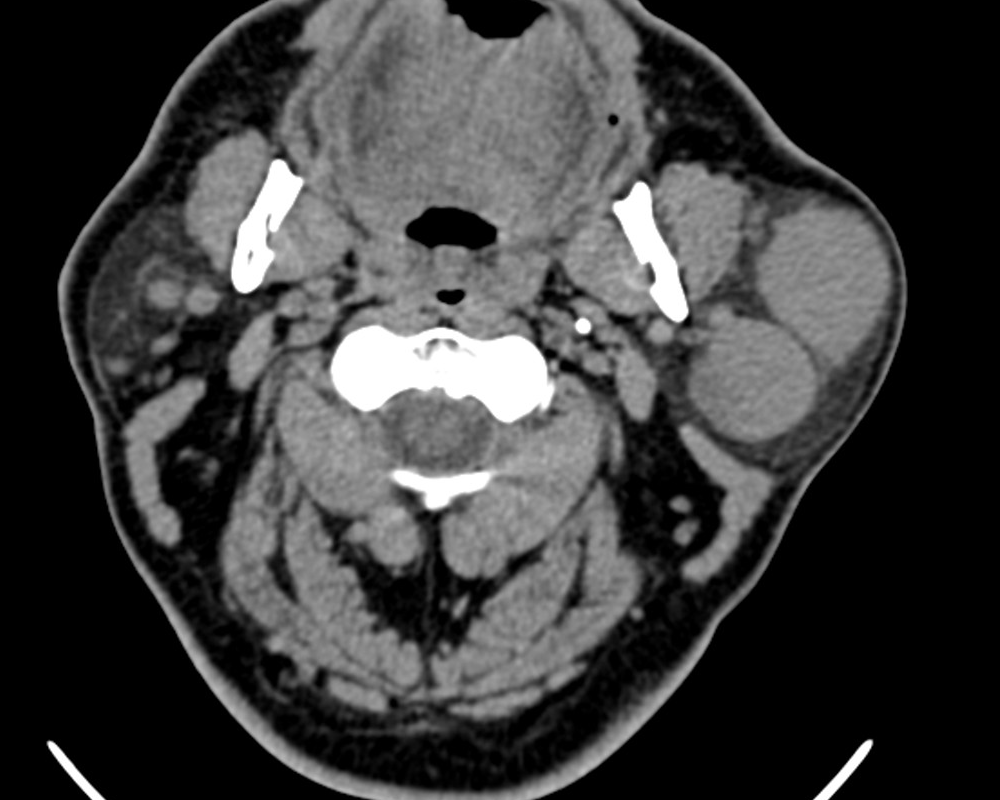

Туморът на Warthin се нарича още цистаденолимфом. Това е доброкачествен тумор на слюнчените жлези с локализация основно в областта на околоушната жлеза - изключително рядко се срещат цистаденолимфоми при подчелюстните и подезичните жлези. Туморът е втората по честота неоплазма на паротидната жлеза - най-често се среща плеоморфният аденом. Не се развива често при млади хора - среща се в периода четвърта - седма декада от живота. Много често има кистозен храктер; хистопатологично се открива папиларен епител в лимфоидна строма, като се срещат и различни по разер кистозни пространства. При около 10 % от случаите туморът се развива билатерално, а в други 10 - 20 % растежът е мултицентричен.

Тумор на Warthin